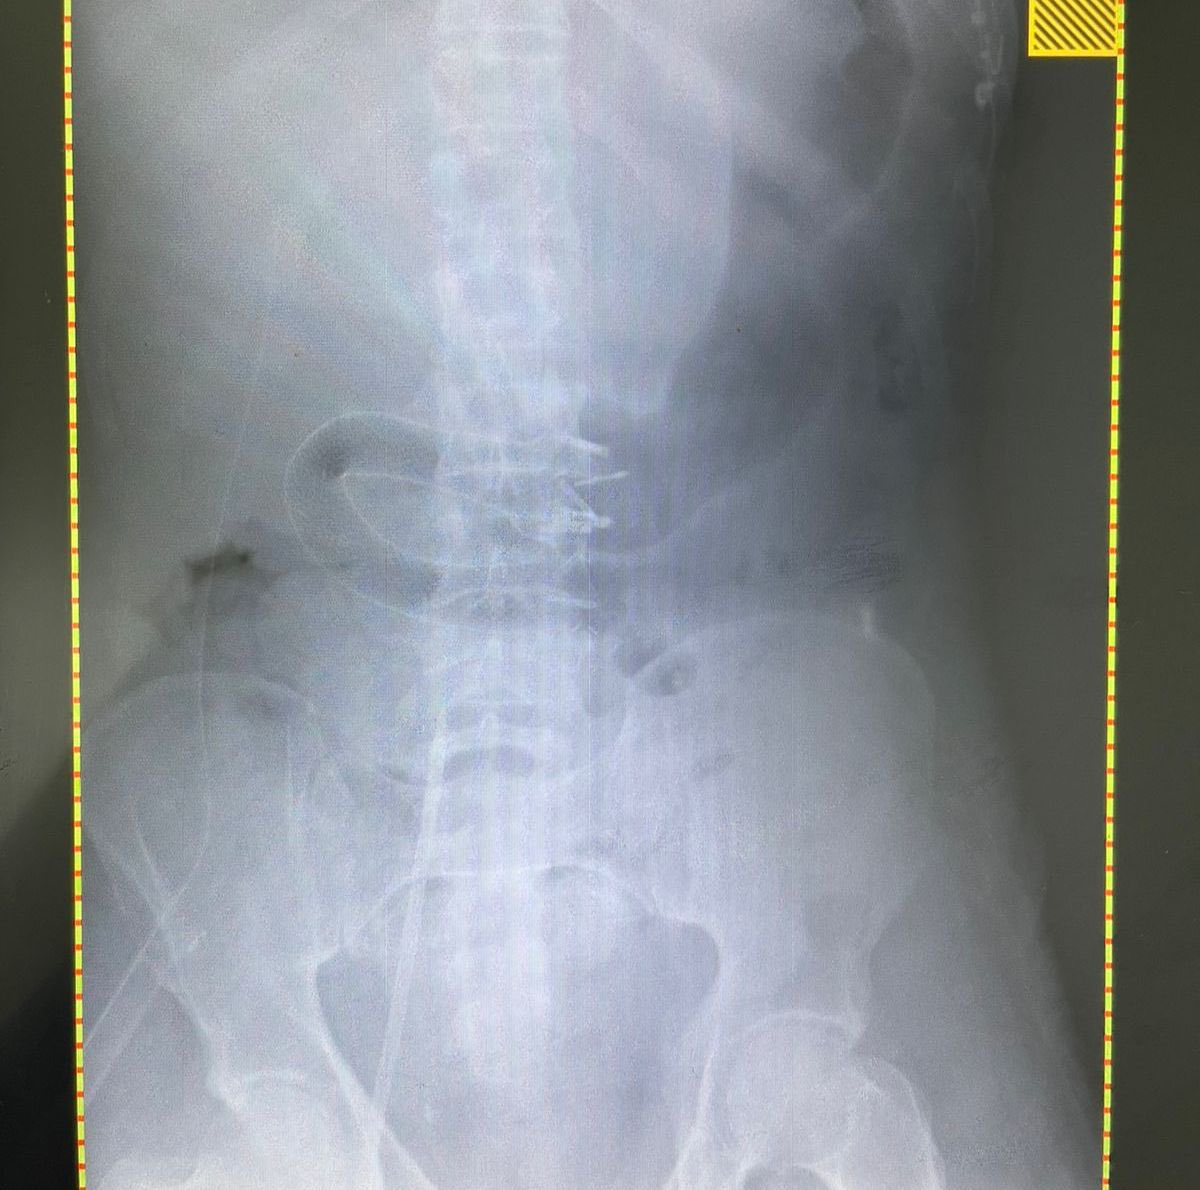

بالمنظار والتعاون الجراحي: وضع دعامه في الامعاء الدقيقة وتثبيتها بالدبابيس من خلال المنظار